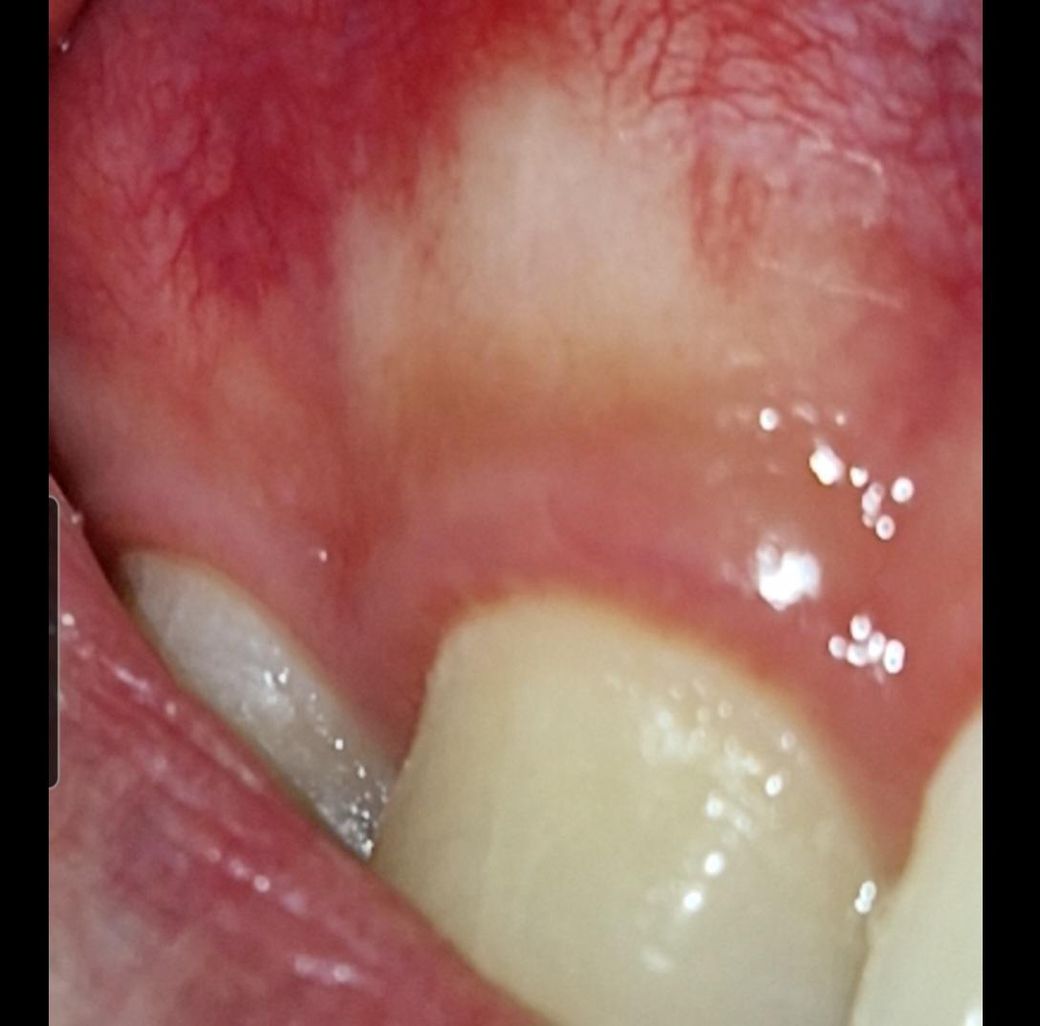

염증? 종양? 궤양? 잇몸이 하얀색이에요.

위 송곳니 잇몸부분이 하얗고 만지면 딱딱하며 다른 부위에 비해 민감하고 따끔따끔 거리는 건 같아요. 그냥 정상적인 구조물인지 병적인건지 궁금합니다.

사진에 보이는 부위가 다른 곳보다 잇몸이 얇아서 보이는 현상입니다. 큰 문제가 잇는건 아니니 너무 걱정하지마세요.

정상적인 것입니다. 그 부위에 잇몸 두께가 얇으면 하얗게 삐쳐 보이는 경우가 종종 있습니다. 그냥 두면 됩니다